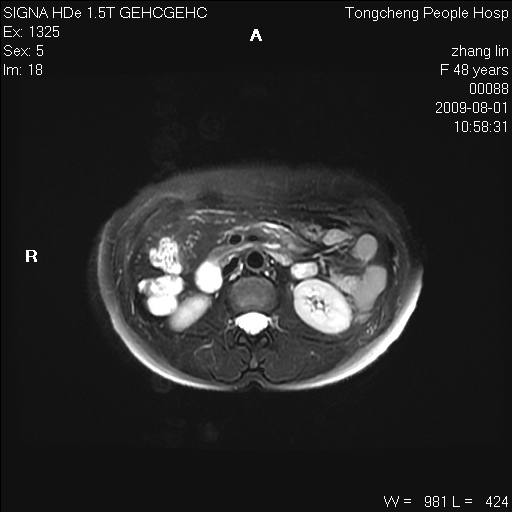

女,48岁。健康体检,彩超发现右肾占位性病变。平素健康。

临床诊断:右肾占位性病变,性质待定(囊肿?肿瘤?)。

上中腹部mr平扫+增强扫描,图像如下:

右肾上极见一类圆形病灶,t1wi呈等信号t2wi呈等高混杂信号,三期增强无强化,边界清---考虑囊肿出血。

同反相位均表现为等信号,病变无强化,考虑含蛋白的囊肿可能,弥散加权相或许有些帮助,

肝囊肿

慢性胆囊炎